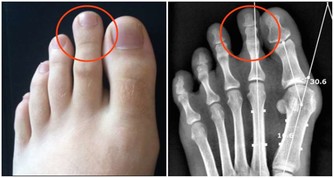

(一)腎小球疾病:急慢性腎小球腎炎、腎病綜合徵等。(二)腎小管間質疾病:1感染性疾病:如腎盂腎炎。2尿路梗阻:如前列腺肥大、尿路結石、後天性尿路畸形等。3腎結核。

(三)腎血管疾病:如腎動脈狹隘、腎動脈硬化、腎靜脈血栓組成等;